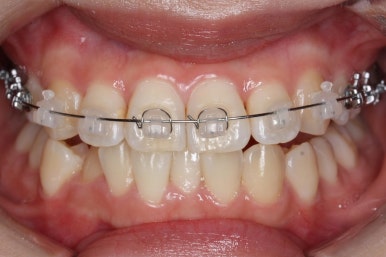

우선 윗니부터 가지런하게 합니다. 그리고 아랫니는 가지런하게 할 준비를 하죠.

화살표에 보이는 부착물의 이름이 바이트터보 입니다.

깊게 맞물리는 앞니, 즉 과개교합을 개선하기 위해 일시적으로 이용하는 장치입니다.

굉장히 효율적으로 과개교합을 개선할 수 있습니다.

아랫니에도 이제 장치를 붙였습니다.

과개교합인 채로 아랫니에도 장치를 붙이게 되면 아랫니 장치가 깨물려서 다 떨어지거나 부서지기 쉽습니다. 따라서 바이트터보는 굉장한 역할을 하게 됩니다.

눈으로 보기에는 과개교합이 개선이 된 것처럼 보이지만 아직은 아닙니다. 바이트터보가 남아있는 채로도 어금니가 맞물려야 진짜로 개선된 것이죠.